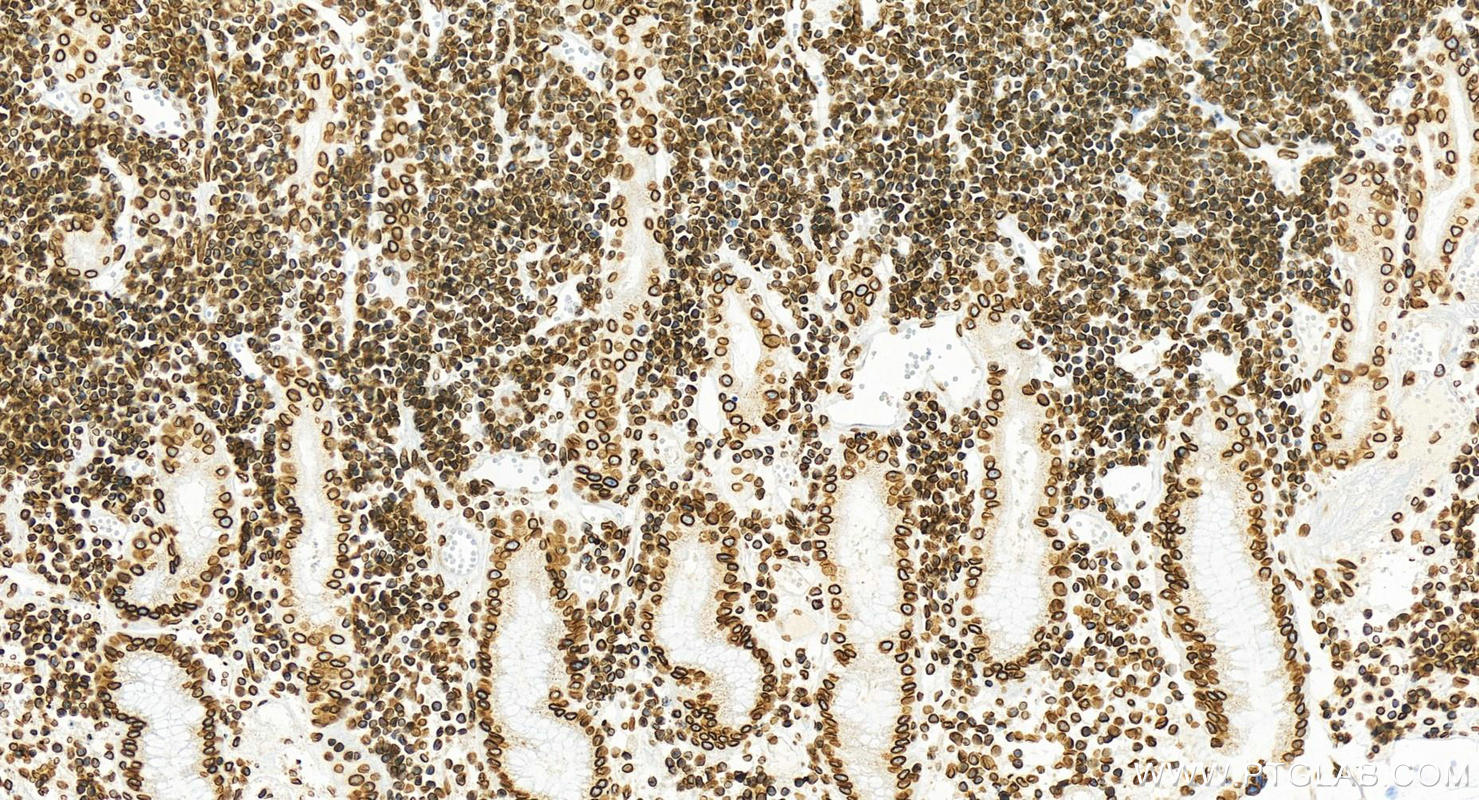

82801-4-PBS targets Lamin B2 in WB, IHC, IF/ICC, FC (Intra), Indirect ELISA applications and shows reactivity with human samples.